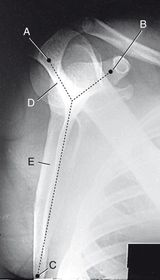

Which projection/position is this? PA Lateral Humerus

Which projections/positions are these? (top->bottom) TOP: Scapular Y-View _________________________ BOTTOM: AP External Rotation (greater tubercle in profile)